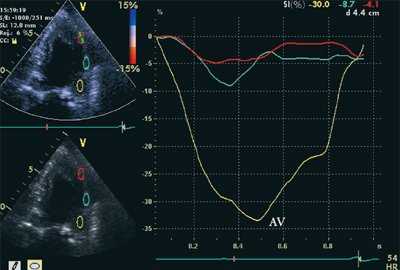

ЭхоКГ (стандартная и в режиме тканевой допплерографии) проводилась на ультразвуковой диагностической системе Vivid Five фирмы General Electric (США) секторным датчиком c частотой 3,75 МГц. Исследовалось движение продольных волокон миокарда в проекциях по длинной оси левого желудочка из верхушечного доступа. Тканевая допплерография проводилась в 4-, 3- и 2-камерной проекциях в каждом из 16 сегментов левого желудочка и в 4 точках митрального кольца: у основания заднеперегородочной, боковой, нижней и передней стенок левого желудочка. Оценивались следующие параметры.

- Пиковая скорость и амплитуда систолической деформации: SR (strain rate) и ST (strain).

- Постсистолическая деформация (STps).

На рис. 3-5 приведены различные варианты ПСУ у больных с постинфарктным кардиосклерозом.

![Кривые деформации миокарда в норме]()

![Кривые деформации миокарда при постинфарктном кардиосклерозе]()

б) При постинфарктном кардиосклерозе. У больного регистрируется высокоамплитудный пик постсистолической деформации (STps).

Вертикальная линия (AV) на рис. 3-5 соответствует времени закрытия аортального клапана. На представленных графиках также отмечается наличие базально-верхушечного градиента (снижение пиковых миокардиальных скоростей, продольного систолического смещения и деформации от основания к верхушке левого желудочка).